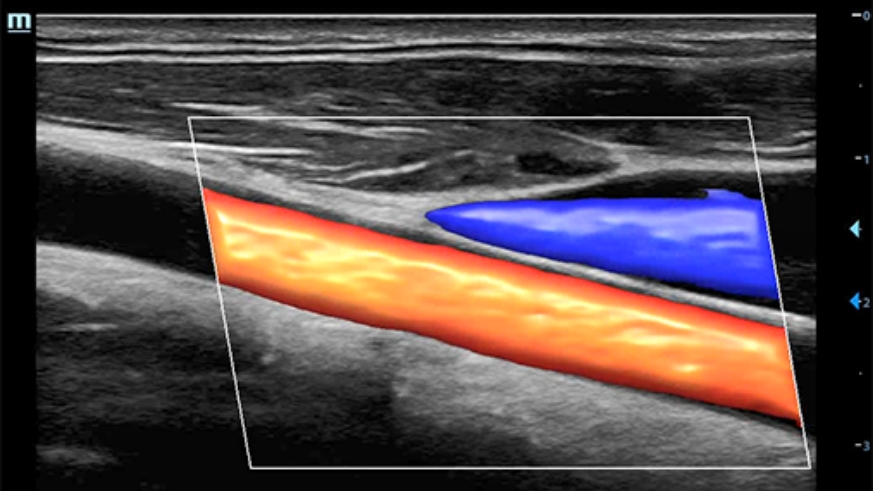

Smart Track

ItŌĆÖs Mindray unique feature to reduce repetitive, time-consuming scanning steps in vascular exams. Smart Track provides intelligent and real-time vessel tracking and real-time image optimization of Color and PW.